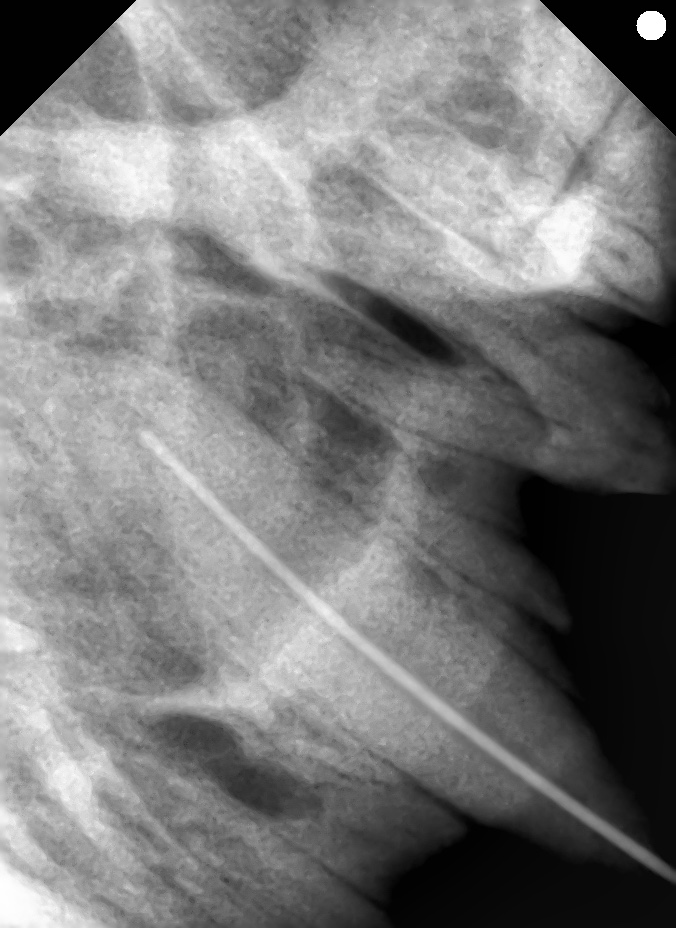

下の写真は犬歯が折れてしまった猫ちゃんです。

レントゲン検査では根尖病変を疑う所見はありませんでしたが、

破折から時間が経ってしまていたため、神経を抜く抜髄治療を行いました。